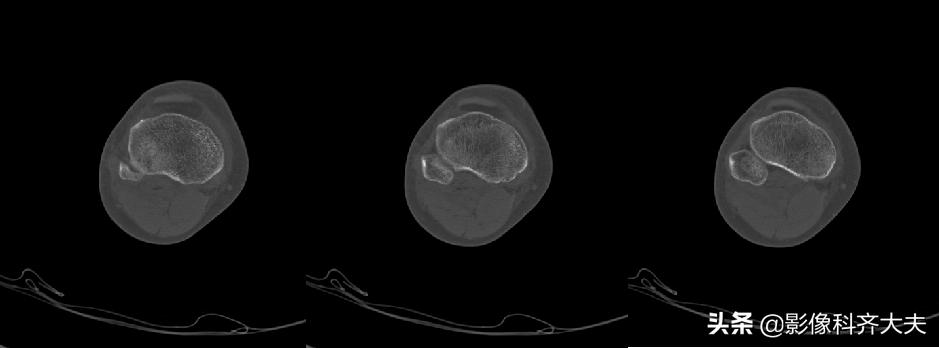

例:右胫骨骨挫伤

右胫骨骨挫伤-平片正常

右胫骨骨挫伤-CT正常

右胫骨骨挫伤-MRI清晰显示病灶位置

胫腓骨骨挫伤

胫腓骨对应性骨挫伤